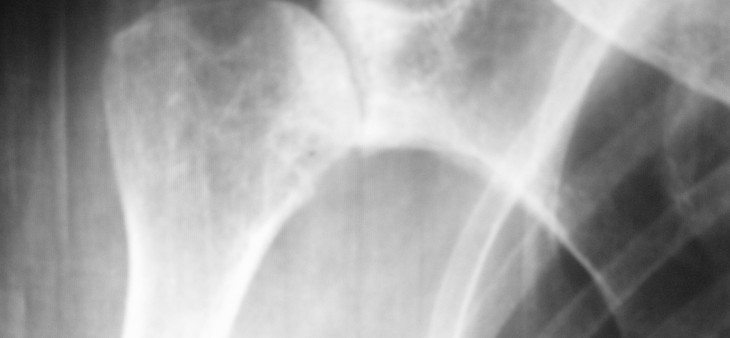

Fraturas Do Ombro

As fraturas que acometem o terço proximal do úmero (ombro) geralmente acometem pacientes idosos por, usualmente, haver nesta faixa etária uma fragilidade óssea (osteoporose), bastando um trauma banal, como uma queda da própria altura, para que ocorra uma fratura. Em pacientes jovens, por terem boa estrutura óssea, as fraturas, em geral, são decorrentes de […]